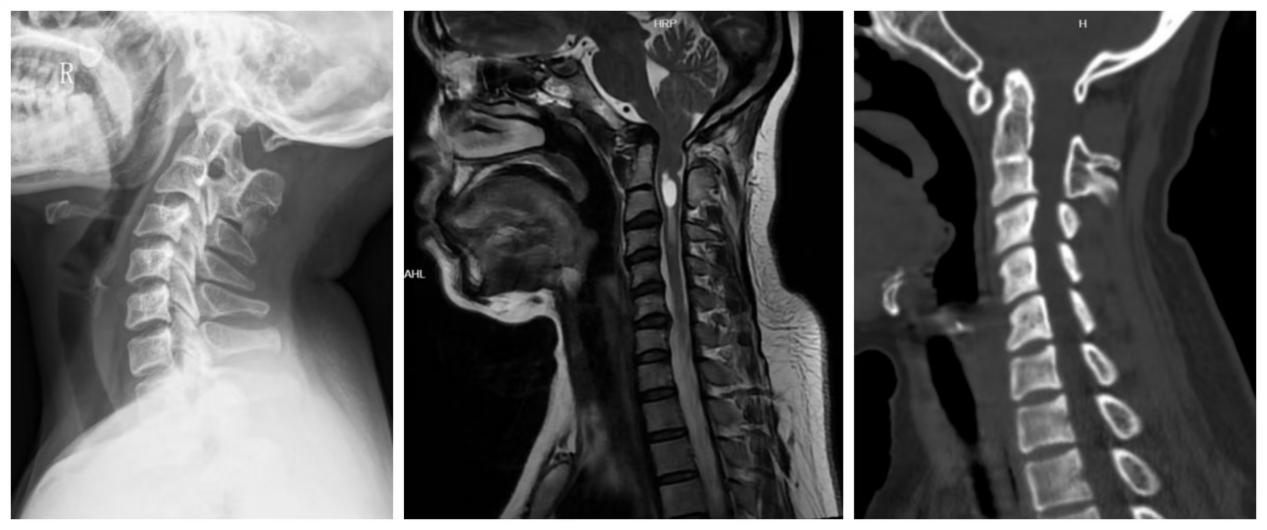

该院神经内科接诊团队为其制定了详细的检查方案,先后完善了颅脑CT、颈椎核磁共振MRI等一系列影像学评估,结果显示李女士存在明显的发育畸形特征。随后神经内科、神经外科和骨科展开了多学科联合会诊(MDT),专家团队最终为其明确诊断为枕颈融合、颈2/3分节不良、颅底凹陷症、枕骨大孔疝、脊髓空洞症。

患者影像学检查显示颅底凹陷、寰枕融合、颈2/3分节不良,伴有枕骨大孔疝,脊髓空洞症